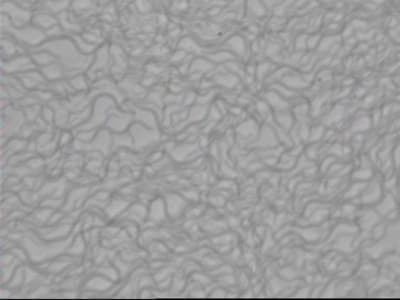

La microscopie initiale de ce cas.

Pas de très belles photos car les bestioles étaient trop vivaces et comme c'était le dernier rendez-vous, je ne me suis pas senti d'attendre trois ou quatre heures que leur activité baisse...

Beaucoup de spirochètes, des trichomonas, quelques entamoebas et des hématies liées au saignement spontané.